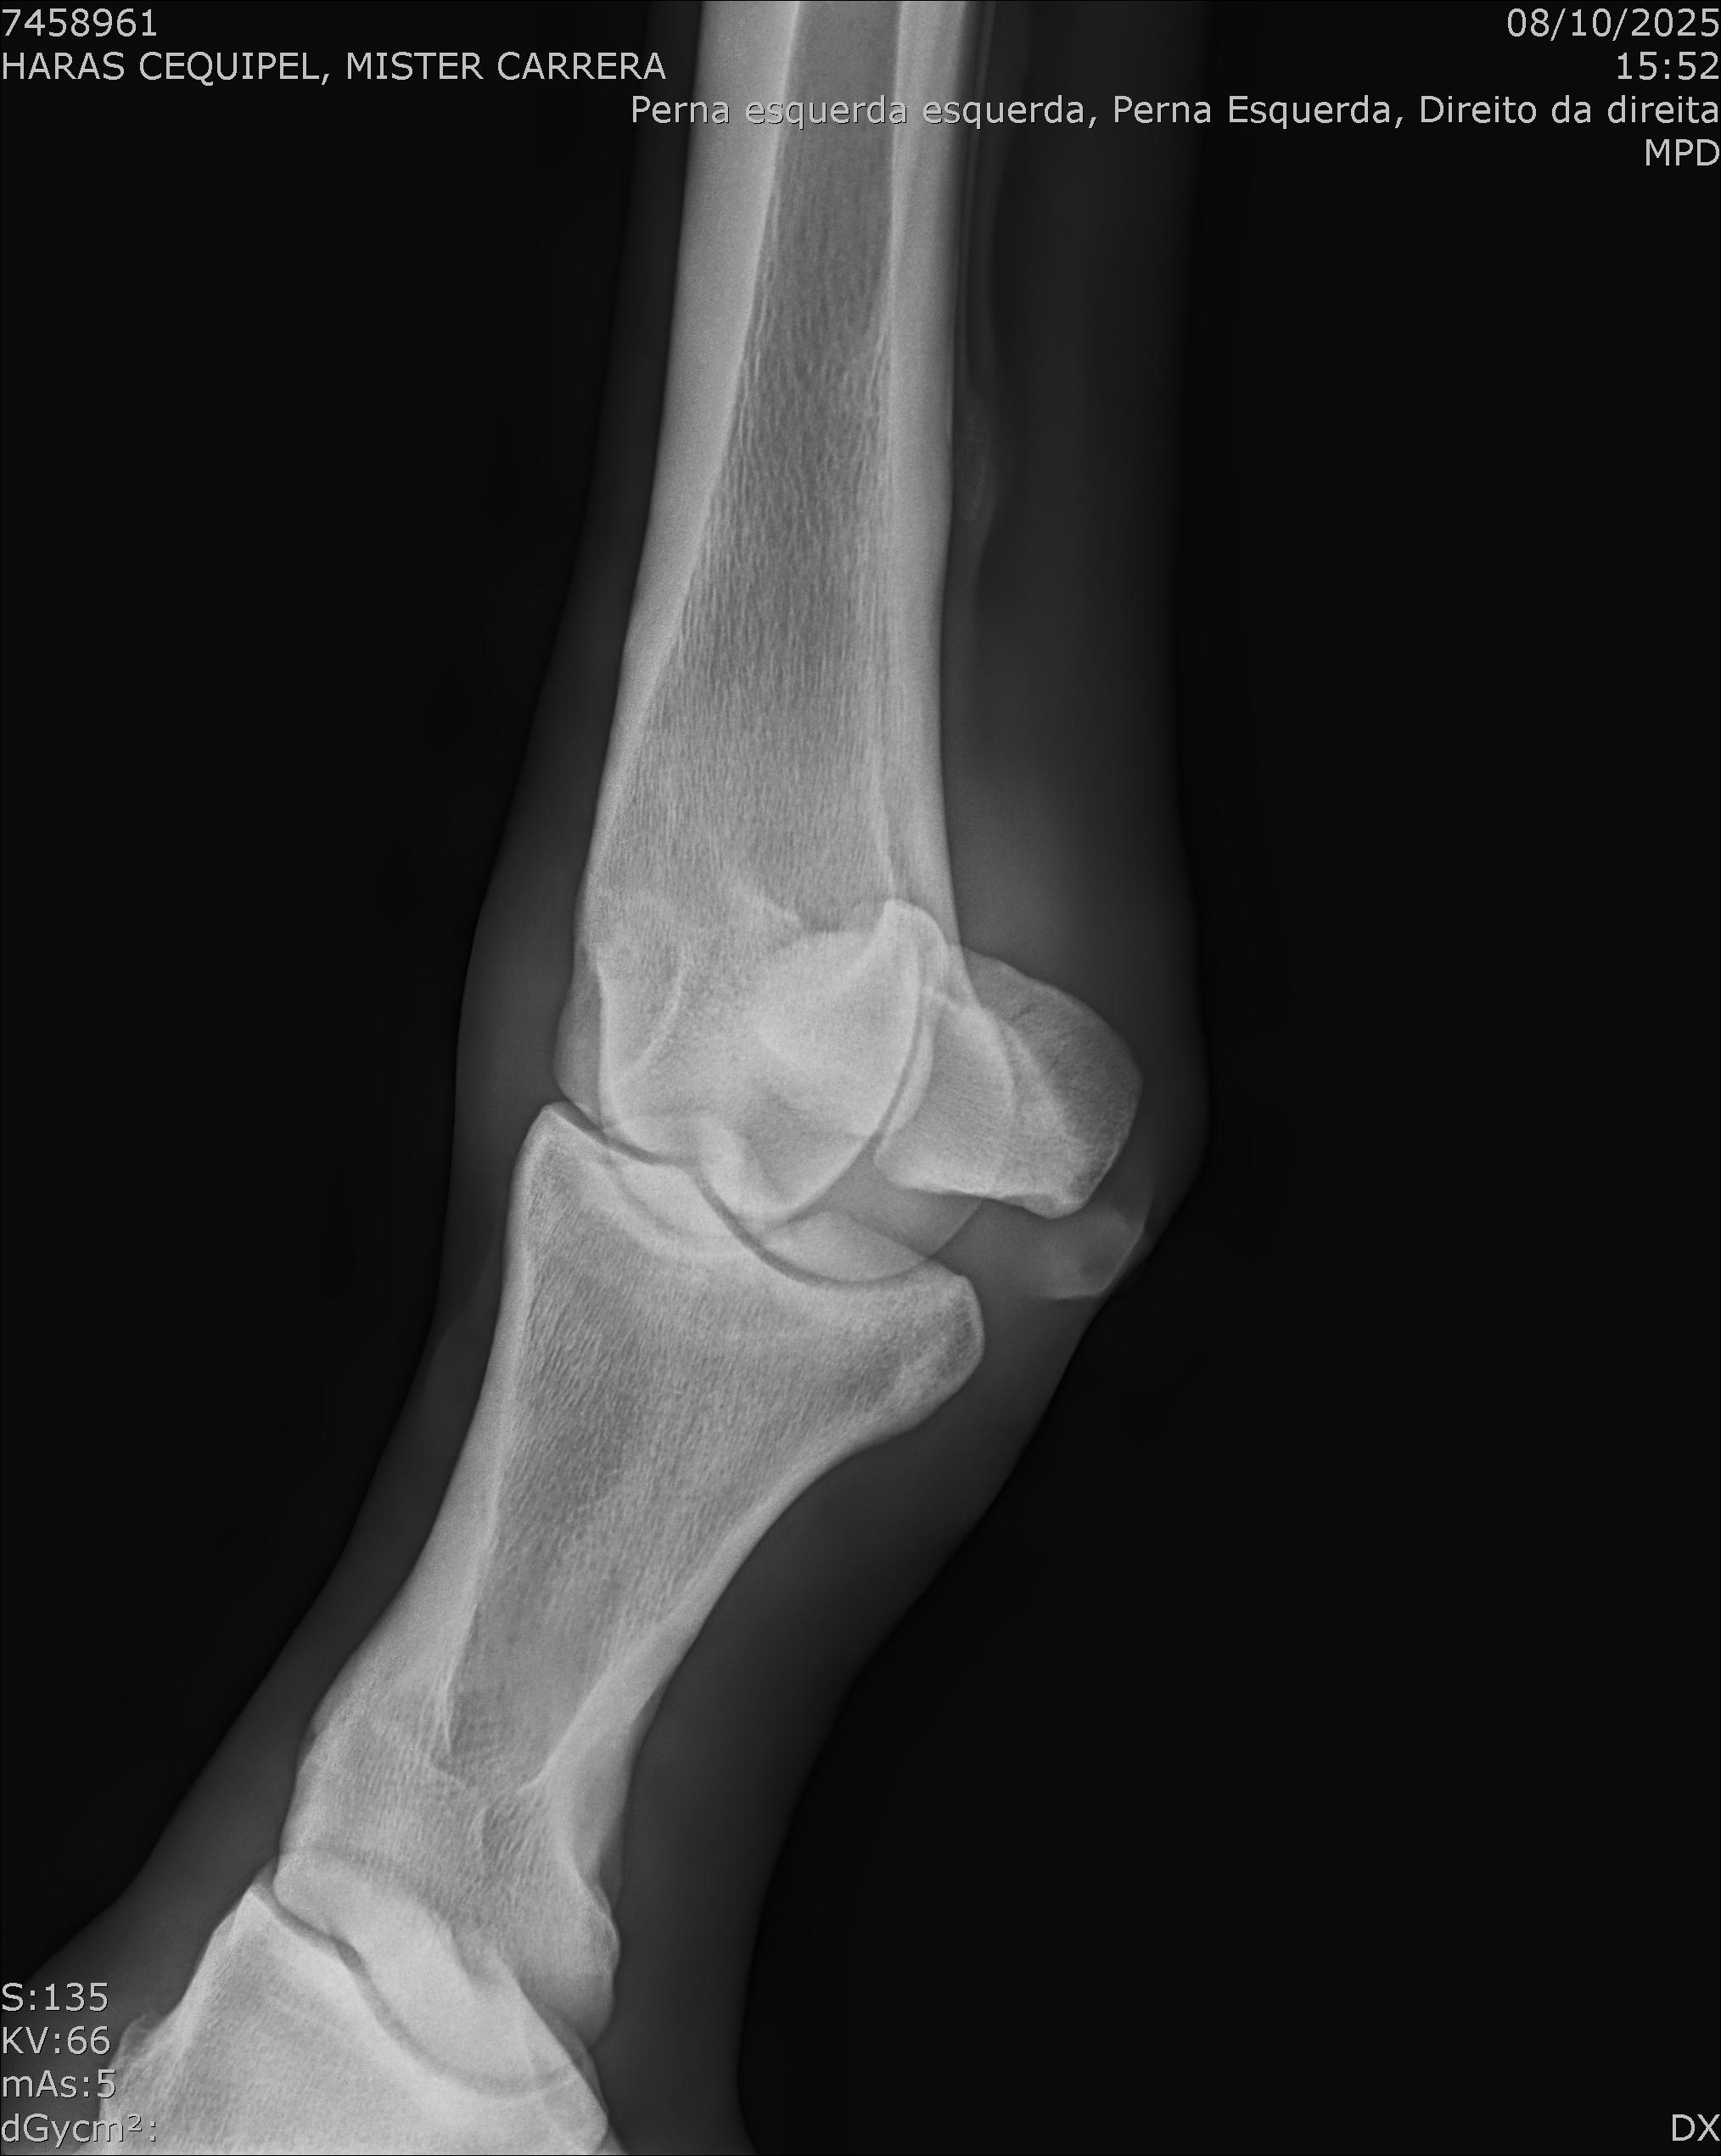

:: RAIOS-X DO LOTE